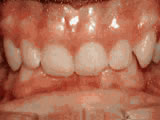

Crowding of the teeth

crowding of the teeth beforeBefore

crowding of the teeth afterAfter

Patient started treatment at age 11 and wore braces for 26 months. He loves his new smile.